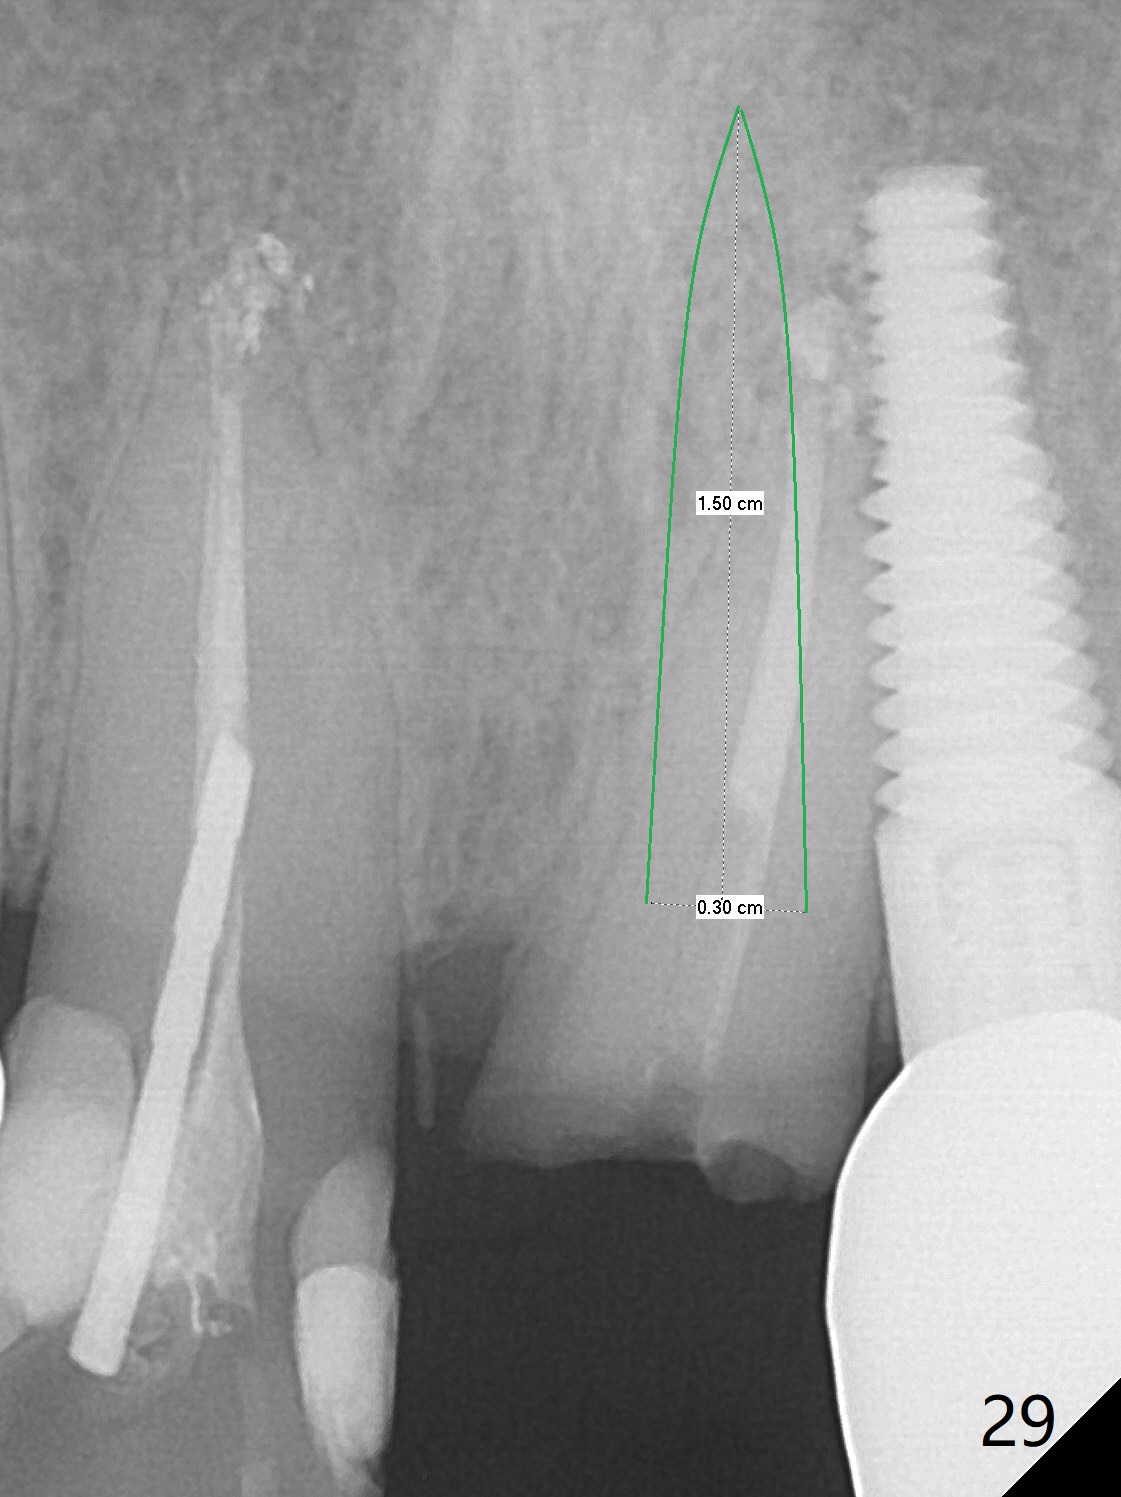

Six months post cementation, the tooth #9 becomes symptomatic.  Is it possible that the implant at #10 is too close to the root of #9?  It is asymptomatic after pulpotomy, but the tooth fractures equi/supragingivally.  Two PAs taken while RCT show osteointegration at #10-12 (Fig.18,19).  While the bone density increases at #10 regular implant, there is minimal bone loss around the 1-piece implants 13 months post cementation (18 months postop, Fig.20,21).  The gingiva remains healthy 19 months post cementation (Fig.22).  76岁病人突然打电话说一个植牙牙冠松动,其实9号牙(自然牙)折裂,6,10-13号牙植牙好像没有骨质吸收(图二十三至二十五),10-13牙位牙龈健康(图二十六,行使功能五年)。9号牙牙冠重新粘固后,显示前牙深覆合,深覆盖(图二十七,二十八)。如果再次脱落需要植牙,选择一段式有助于植入和修复,因为植体和基台直径小。两段式植牙相对基台直径至少4,或者4.5毫米,前牙修复显得笨重。由于9,10牙根和植体接近,9号牙植体需要偏小而长,3x14或者15毫米(图二十九)。